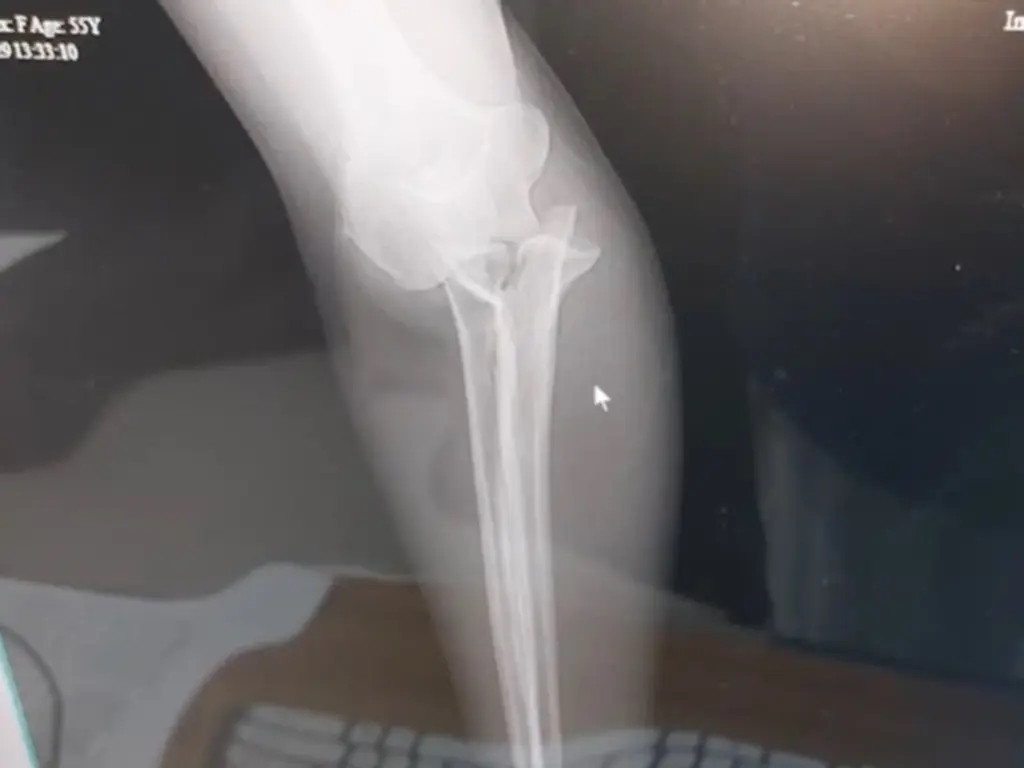

"Tay tôi bị dập nát, bên trong đó là rất nhiều nẹp và đinh vít để cố định phần tổn thương", Beth nói.

| Phim chụp X-quang cánh tay của Beth gãy dập sau khi bị voi cắn. Ảnh: WMUR. |